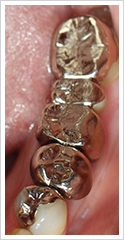

メタルの下に二次むし歯があった為、被せ物を除去し虫歯を取り除いた後口腔内スキャナーで撮影を行い、セラミックインレーで修復しました。

| 患者の主訴や症状 | 知人の紹介で来院 被せ物のやり変え希望 |

| 治療の内容や方法 | 左下3本メタルインレーの下に2次むし歯が起こっていた為 メタルインレー・むし歯を除去し、セラミックインレーをセット。 残りの1本は神経を抜く治療が必要であった為、根管治療を行い コアを立て、院内にてジルコニアクラウンを製作しセットしました。 |

| リスク | 保険がきかない自由診療 むし歯が深い場合は他の治療と同様に痛みが出る場合がある |

| 治療回数・治療期間 | セラミックインレーセットまで 通院回数 2回 ジルコニアクラウンセットまで(根管治療含む)治療期間 約7ヶ月 |